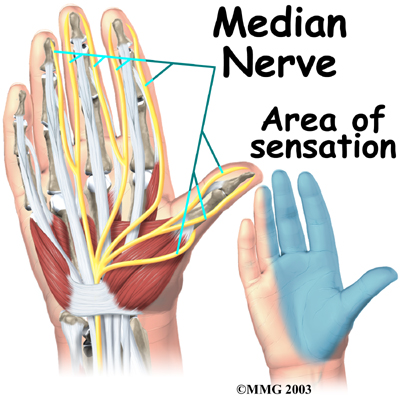

All of the nerves that travel to the hand and fingers begin together at the shoulder: the radial nerve, the median nerve, and the ulnar nerve. These nerves carry signals from the brain to the muscles that move the arm, hand, fingers, and thumb. The nerves also carry signals back to the brain about sensations such as touch, pain, and temperature.

The travels through a tunnel within the wrist called the carpal tunnel. This nerve gives sensation to the thumb, index finger, long finger, and half of the ring finger. It also sends a nerve branch to control the thenar muscles of the thumb. The thenar muscles help move the thumb and let you touch the pad of the thumb to the tips each of each finger on the same hand, a motion called opposition.